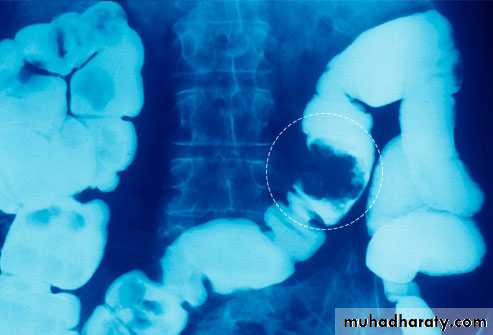

Barium enema examination demonstrates loss of haustral folds in the entire descendingcolon with small ulcerations suggested. The colon has a "lead-pipe" appearance. The distribution and appearance are suggestive of ulcerative colitis.

o Shortening of the colon-may be from spasm of longitudinal muscles or from irreversible fibrosis (lead-pipe colon)

o Loss of haustrations on left side of colon